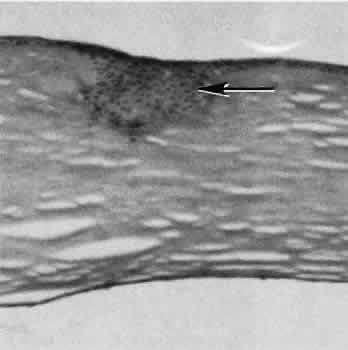

Penetrating corneal injuries involving at least one third of the stroma (Fig. 4) are covered initially by proliferating surface epithelium that may extend for a considerable distance into the stroma. The extent of corneal epithelial migration is controlled at least in part by contact inhibition of migration once contact with healthy corneal endothelial cells is established.21 Bowman's membrane has elastic properties that tend to pull the anterior margins of the wound apart. Exposure of the relatively dehydrated corneal stroma to tears and blood will cause swelling of the corneal stroma. This swelling of the stroma tends to close the wound. As the stroma heals, new collagen is produced by keratocytes or transformed monocytes. Epithelial cells will regress toward the surface. The repair collagen is different from the native collagen in size and in orientation. The healed wound is densely opaque and obvious clinically, but it may be detected histologically only by the break in Bowman's membrane.

Fig. 4. Deep stromal defect. In the area of the defect (right) the epithelium is hyperplastic, Bowman's membrane is absent, and the corneal stroma is thinned. A stromal scar is characterized by and increased number and haphazard arrangement of keratocytes. (Hematoxylin-eosin stain; × 100.)